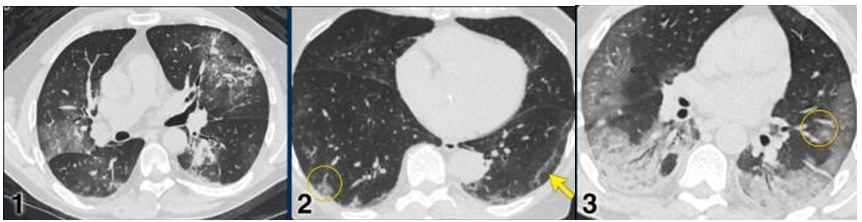

CO-RADS 5: Hình 8 & 9

Hình 8:

Trường hợp 1: Tổn thương đa ổ dạng GGO & đông đặc

Trường hợp 2: Tổn thương đa ổ dạng GGO kèm theo giãn mạch (vòng tròn) & dải băng dưới màng phổi (mũi tên)

Trường hợp 3: Tổn thương GGO & đông đặc cả 2 bên xu hướng vùng sau ngoại vi & nền phổi kèm theo giãn mạch (vòng tròn)